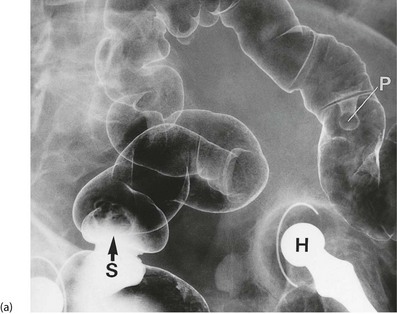

Fig. 27.1 Colorectal polyps

(a) This 65-year-old man was found to have positive faecal occult blood on colorectal cancer screening. This CT colography image shows a solitary polyp in the sigmoid colon, later removed by colonoscopic snaring. It proved to be a benign adenoma. (b) A 2 cm polyp on a long stalk in the sigmoid colon. (c) The snare loop is tightened around the stalk of the polyp before applying diathermy current to remove it and coagulate the blood vessels in the stalk. (d) Adenomatous polyp having mainly villous glandular architecture. The example shown has a well-defined stalk S, although this is more typical of tubular or tubulo-villous polyps, villous adenomas often having a broad base